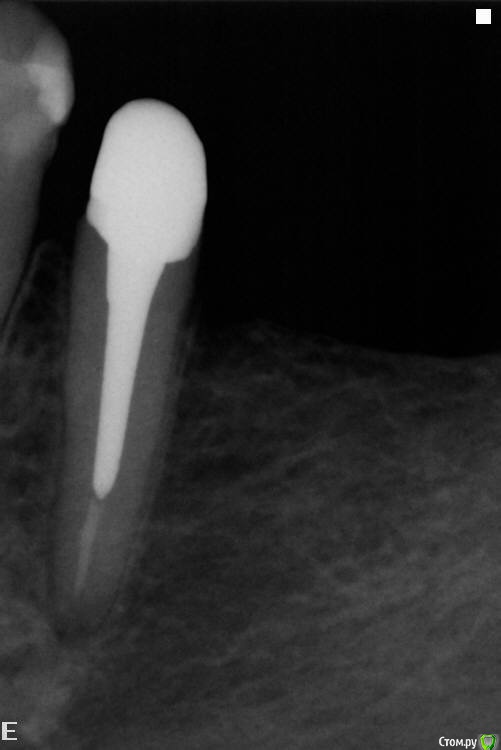

Slaggy Опубликовано 10 сентября, 2015 Поделиться Опубликовано 10 сентября, 2015 паттерн отлипает от стенок. Ему только застыть надо дать время. И кончики твердеют. Не спешите просто.Вазелины шмазелины снизят точность - как вы проконтролируете толщину слоя вазелина в глубине канала?Не пересушивайте канал и будет щастье вам.Вот вопрос чем извлекать вкладку после примерки возникает иногда. Садятся-то они без зазора.... пришло из лабы - ленивые удалено администратором литник не убрали даже, фуджи прилип немного в апроксималке, контрольповерхность завальцована ультразвуком - извлекал после примеркикорень был скрыт под десной- удлинял, отсюда такой вид По поводу врещения - есть 2 вида геморроя:1- паттерн застыл и вы извлекли недовкладку - будет вертеться при обработке, нужно придерживать2- паттерн застыл и сразу обрабатываем - сложно извлечь готовую вкладку не сделав на ней следавыбираем как сегодня будем страдать и начинаем ))))) 1 Ссылка на комментарий

Slaggy Опубликовано 10 сентября, 2015 Поделиться Опубликовано 10 сентября, 2015 Я много лет делал непрямым - был отличный техник, садилось все великолепно.Сейчас в лабе хорошее литье (на фото) и кривые руки (там-же), поэтому стал делать прямым.Точность одинаковая - цемент не виден по шву.Я часто уступ точу уже по вкладке, поэтому толщина/нависание края меня мало занимают. Ссылка на комментарий